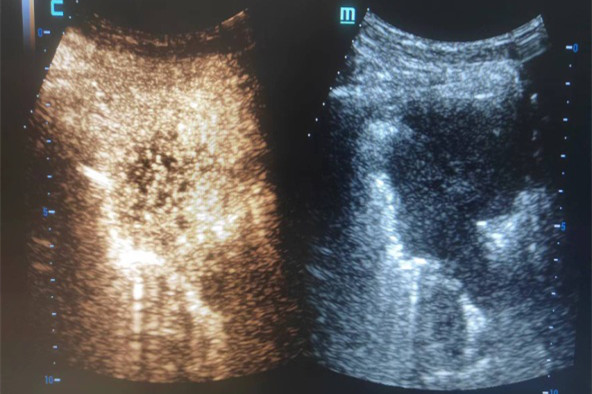

超声造影作为超声检查的一种新型检查方式,是通过观察组织的微灌注情况来判断肿块的良恶性,目前广泛应用于腹腔各脏器肿瘤及甲状腺、乳腺等浅表肿瘤的检查。穿刺术中的超声造影,可以显示肿块内及周边的血管分布情况,区分肿块组织的活性区域,有效指引操作者避开穿刺路径上的大血管和病灶内坏死区域,提高穿刺活检的成功率,减少并发症的发生。相对于传统的X线引导下穿刺活检,具有无放射性、实时、精准、全程显示穿刺针道、安全、高效等优势。

在院领导的大力支持下,我院超声科大力发展超声介入亚专科,北区超声科团队已常规开展甲状腺细针穿刺、乳腺、浅表肿块、肝脏、肾脏、腹腔肿块的超声造影及粗针穿刺活检、甲状腺囊肿、肝肾囊肿的硬化治疗、胸腹腔积液的引流、肝脓肿、梗阻性黄疸经皮胆道(PTCD)及胆囊穿刺(PTGD)引流等。